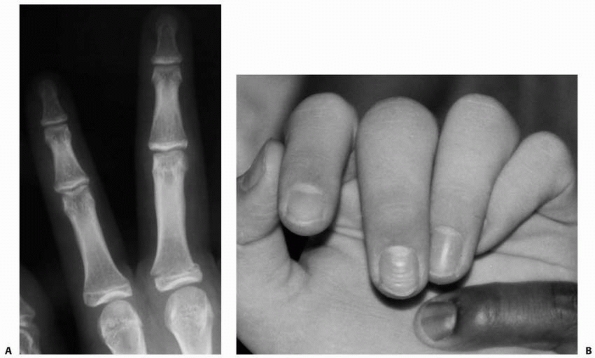

![]() |

FIGURE 8-29 A. An extra-octave fracture in a 12-year-old girl. B. The fracture was reduced with the MCP joint in full flexion.